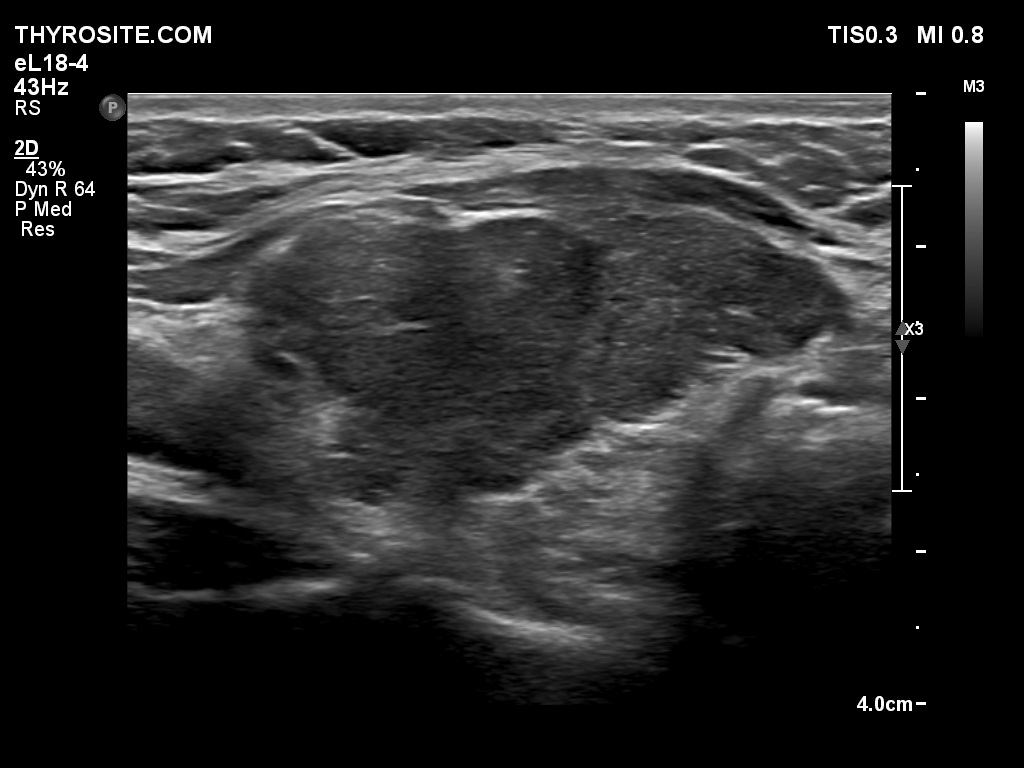

One year after surgery (third row of images)

Ultrasonography: There was no parenchyma according to the right lobe, while there was a relatively large thyroid tissue in the left lobe. The latter displayed increased vascularization.

TSAb was undetectable. The replacement therapy has stopped. We offered regular follow-up.